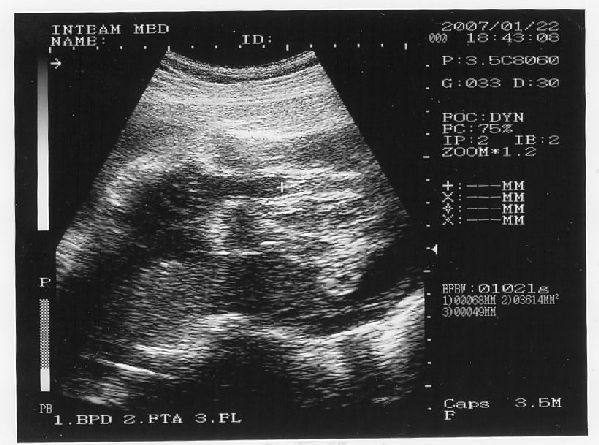

Tényleg tündéri pofija van, nagyon megható lehetett látni. Gondolom sokkal szívhez szólóbb, mint mikor az egész babát látni. Ez már személyesebb lehet.

Gabi baba arcocskája

Gabi baba arcocskája  Gabi baba kukaca

Gabi baba kukaca